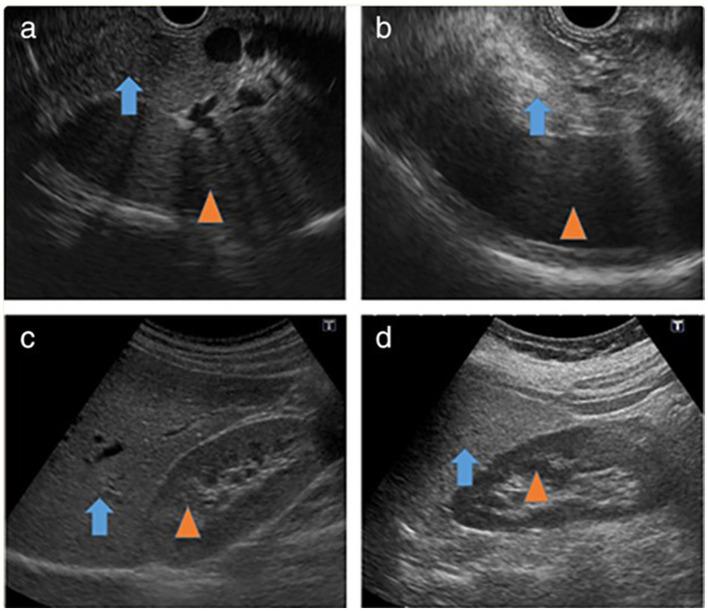

Fatty infiltration of the pancreas (FIP) has been recognized for nearly a century, yet many aspects of this condition remain unclear. Regular literature reviews on the diagnosis, consequences, and management of FIP are crucial. This review article highlights the various disorders for which FIP has been established as a risk factor, including type 2 diabetes mellitus (T2DM), pancreatitis, pancreatic fistula (PF), metabolic syndrome (MS), polycystic ovary syndrome (PCOS), and pancreatic duct adenocarcinoma (PDAC), as well as the new investigation tools. Given the interdisciplinary nature of FIP research, a broad range of healthcare specialists are involved. This review article covers key aspects of FIP, including nomenclature and definition of pancreatic fat infiltration, history and epidemiology, etiology and pathophysiology, clinical presentation and diagnosis, clinical consequences, and treatment. This review is presented in a detailed narrative format for accessibility to clinicians and medical students.

胰腺脂肪浸润(FIP)已被认识近一个世纪,但这种病症的许多方面仍不清楚。定期对FIP的诊断、后果及管理进行文献综述至关重要。这篇综述文章强调了已确定FIP为风险因素的各种疾病,包括2型糖尿病(T2DM)、胰腺炎、胰瘘(PF)、代谢综合征(MS)、多囊卵巢综合征(PCOS)和胰腺导管腺癌(PDAC),以及新的研究工具。鉴于FIP研究的跨学科性质,涉及广泛的医疗保健专家。这篇综述文章涵盖了FIP的关键方面,包括胰腺脂肪浸润的命名和定义、历史和流行病学、病因和病理生理学、临床表现和诊断、临床后果及治疗。本综述以详细的叙述形式呈现,以便临床医生和医学生查阅。